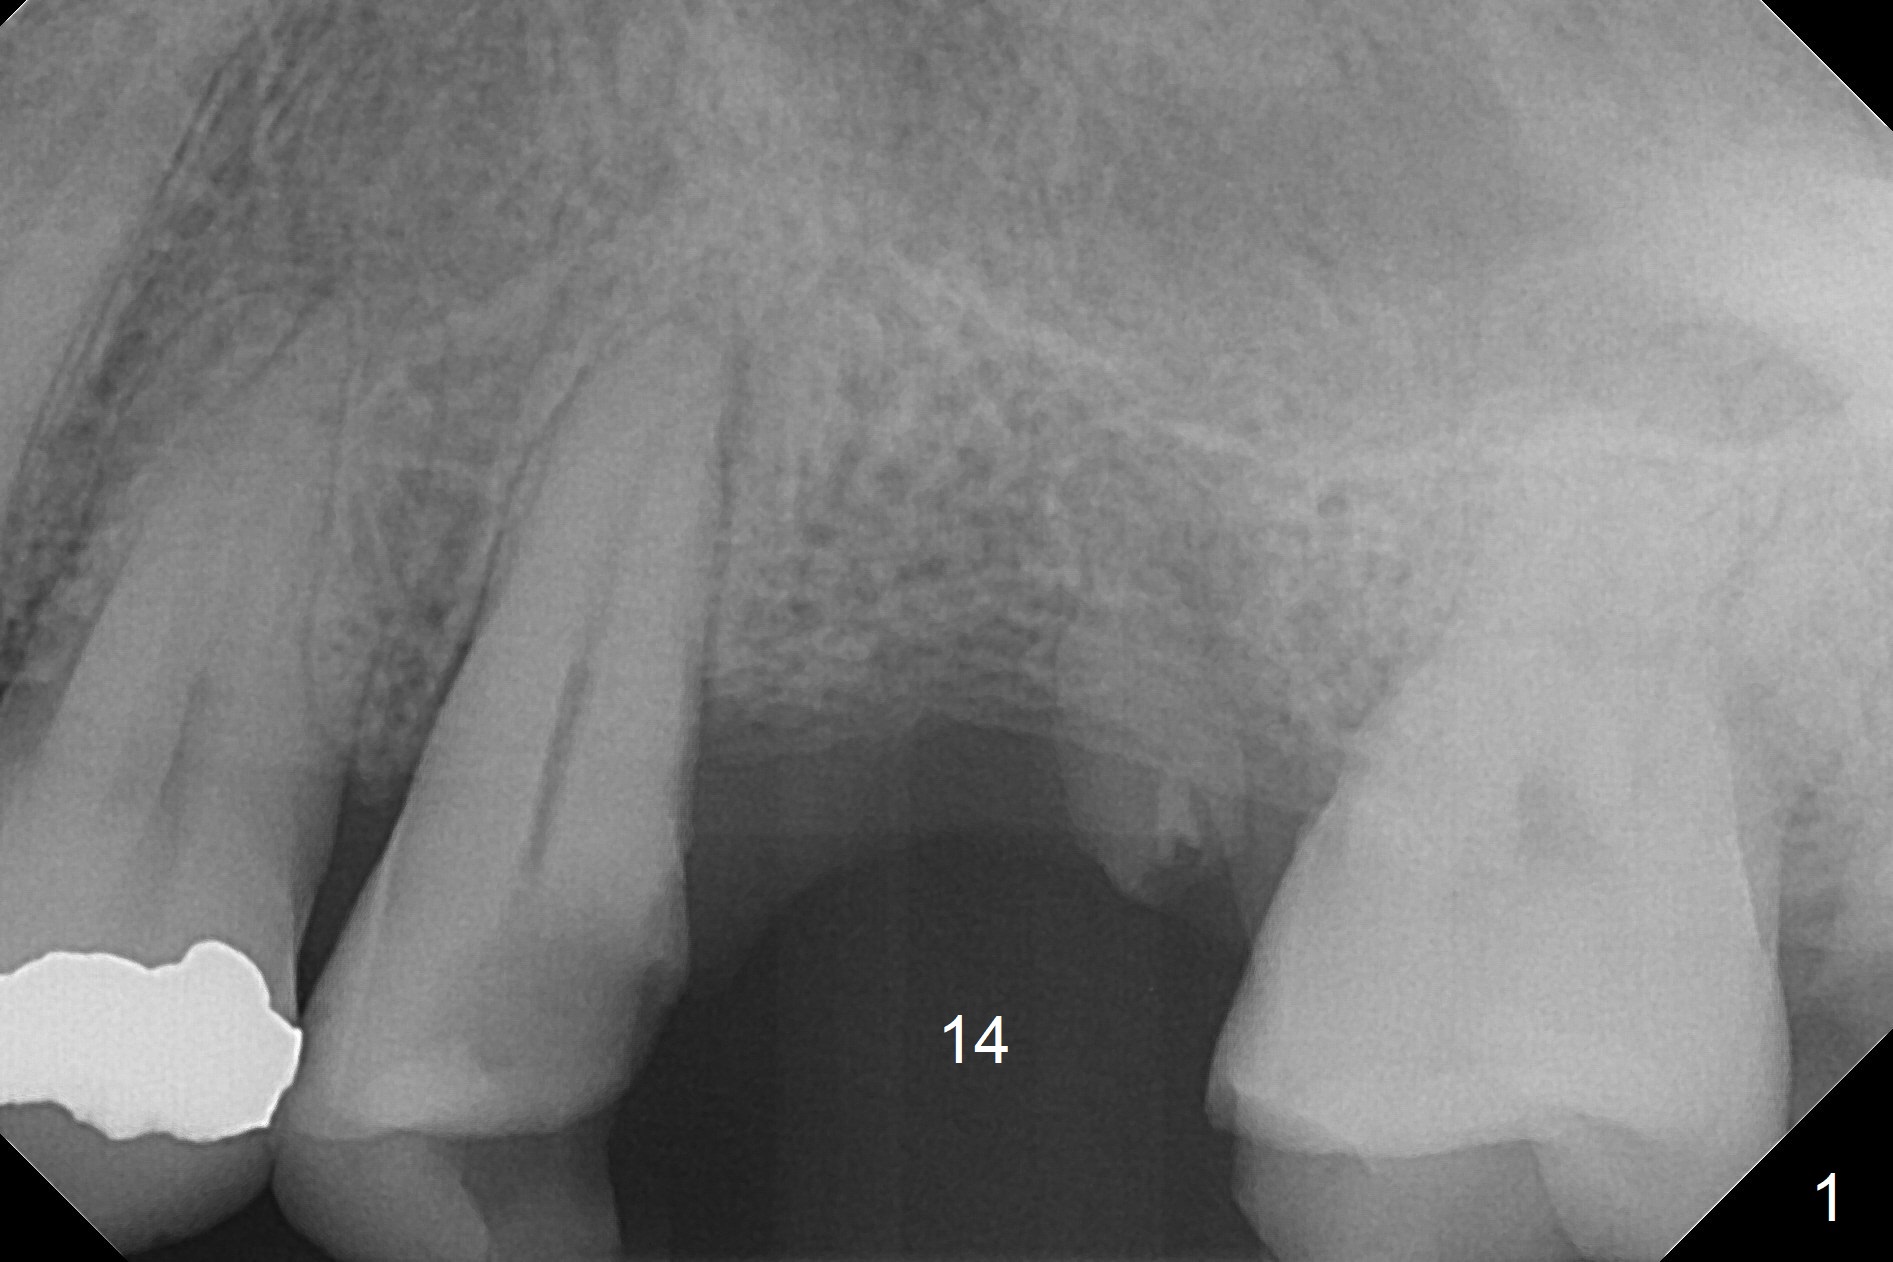

A 37-year-old man will return for #14 extraction and implant after RCT at #13 (Fig.1). After extraction (Fig.2), use Magic Expander (ME) along the long axis of the socket to initiate osteotomy shy of the sinus floor (Fig.3 (<9 mm gingival level)) and change the trajectory at the same time (Fig.4 white arrow). Take the 1st intraop PA when a small ME is stable. Gradually increase the depth for sinus lift as the diameter of MEs increases (Fig.5). Take preop photos to show the residual root and the alveolus (whether it is atrophic or not). Place bone graft (Fig.6 red circles) prior to dummy implant (green).